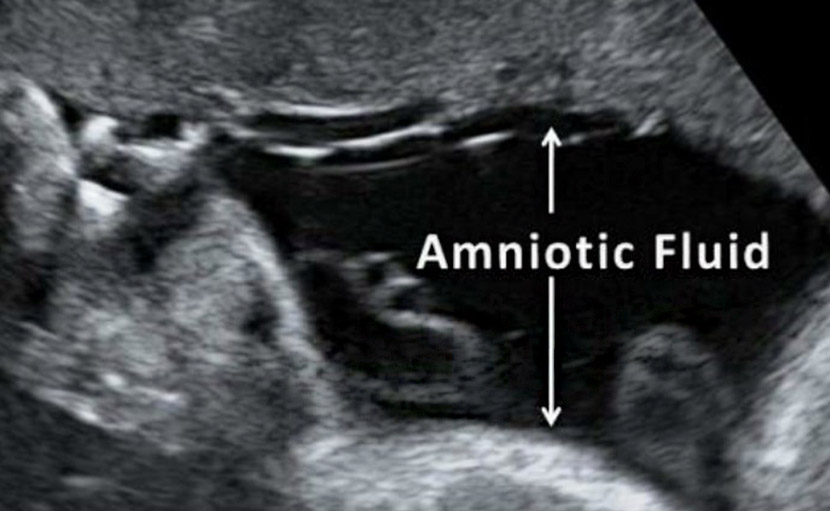

গর্ভাবস্থায় পানি ভাঙ্গা সম্পর্কে কতটুকু জানেন?

0 SHARES Share Tweet গর্ভাবস্থায় পানি ভাঙ্গা সম্পর্কে সঠিক ধারণা আমাদের অনেকেরই নেই। সাধারণত অ্যামনিওটিক মেমব্রেন রাপচা...